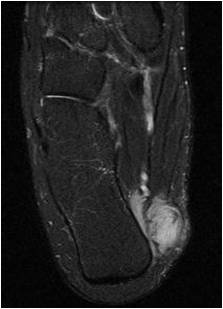

Fig. 3 & 4: MRI Sagittal (Fig. 3) and Coronal (Fig. 4) T2 weighted images of the right foot show a well-circumscribed soft tissue mass with high signal intensity admixed with some hypointense areas, located along the posterior and medial aspect of the calcaneous bone.